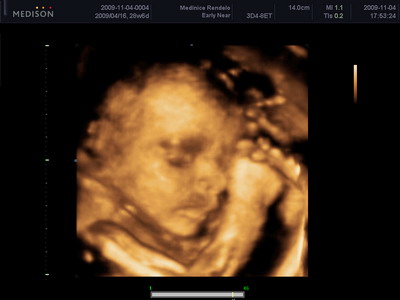

Rólunk röviden, tegnap voltunk mi is 4D-n, Bence már kb. 1283 grammocska, fejjel már a "kijárat felé" néz

, kicsit kalandos volt a vizsgálat, de aranyos képek lettek, és még a férfiasságát is tisztán megörökítették nekünk.

Majd teszek fel képet!

méretei:

BDP: 71,7

HC: 260,26

AC: 241,48

FL: 49,95 (hát nem lesz egy hosszú combú gyerek, de lehet, hogy rosszul mérték

)

Bence 29. héten